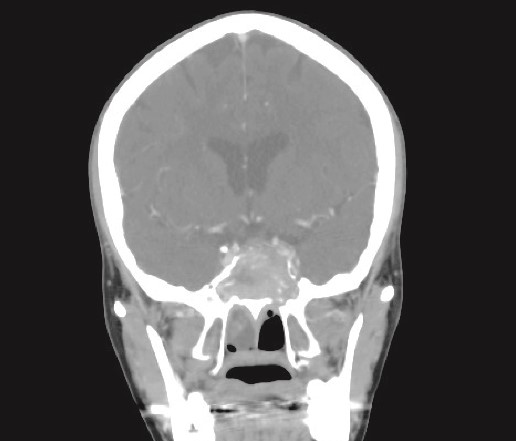

CT brain, coronal reconstruction shows bilateral near total opacification and expansion of the paranasal sinuses and nasal cavity. Invasion of the left cavernous sinus with encasement of cavernous segment of left ICA. Pituitary gland and optic chiasm displaced superiorly.

Patient presented to the emergency department with four days history of sever left side headache associated with nausea and vomiting, and nasal discharge with on\off nasal obstruction. Two days history of diplopia with lateral gaze of the left eye, with decrease the visual acuity. Ophthalmologic examination revealed left abducens nerve palsy. Other neurologic examinations were within normal. Endoscopic nasal examination revealed left multiple grade two nasal polyps occupying the middle meatus. Pre-operative brain computed tomography (CT) shows bilateral near total opacification and expansion of the paranasal sinuses and nasal cavity (Fig. 1). Additionally, there is evidence of invasion of the left cavernous sinus with encasement of cavernous segment of left internal carotid artery (ICA). Furthermore, pituitary gland and optic chiasm displaced superiorly. Magnetic resonance imaging revealed that the sphenoid sinus is expanded and bulging superiorly into the pituitary fossa causing displacement of pituitary gland and stalk without mass effect upon the optic chiasm (Fig. 2). It extends laterally causing effacement of the cavernous sinus and left Meckel’s cave. No evidence of intracranial extension. The patient underwent functional endoscopic sinus surgery with computer-assisted navigation system. Intraoperatively, sphenoid sinus was full of fungal mud and mucin (Fig. 3). The polyps were removed completely from the nasal cavities, fungal mud, and mucin were removed from the sinuses (Figs 4 and 5). Patient had dramatic improvement after surgery, the rhinosinusitis symptoms are resolved, the diplopia has been improved, and the paranasal sinuses were clear. The patient was discharged with topical corticosteroid and saline irrigations.